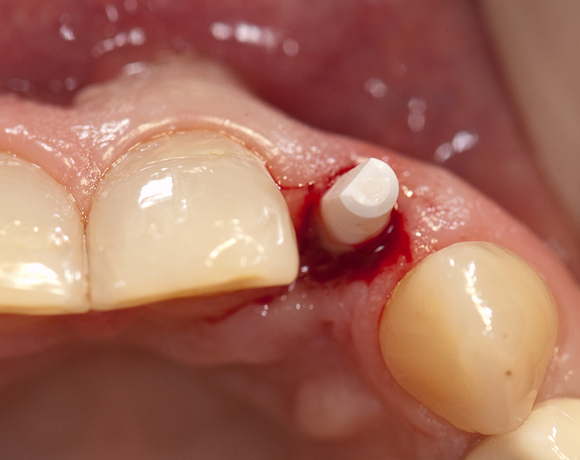

Im vorliegenden Patientenfall musste der Zahn 22 nach erfolgloser Endodontie entfernt werden. Die Nachbarzähne waren kariesfrei, es wurde eine Marylandbrücke (eine Brücke mit zwei Flügelchen, die palatinal an den Nachbarzähnen verklebt werden) oder ein Implantat besprochen. Die Patientin hat sich für ein Vollkeramikimplantat entschieden. In der Diashow wird der operative Eingriff bis zur fertigen Krone gezeigt. Die Einheilzeit betrug drei Monate.